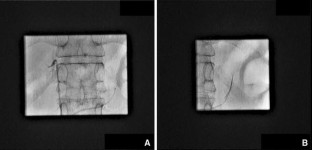

Fig. 2